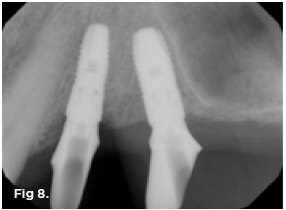

Fig 8. Tilted implant solutions for maxillary posterior partial edentulism. In the same manner that tilted implants can be used to

avoid the need for sinus grafting in full-arch implant prostheses, they can be used to avoid direct or indirect sinus grafting when insufficient posterior

maxillary bone volume challenges a fixed dental prosthesis implant restoration. Fig 7: Software planning for implant placement is shown with

tilting of the distal implant along the anterior wall of the maxillary sinus where there is insufficient bone in zone 3. Fig 8: Postoperative radiograph

of the implants and abutments reveals the angulation of the implant resolved by the CAD/CAM abutment. Fig 9: Final radiograph of the implant

prosthesis following restorations demonstrates the inclusion of a tooth in the molar position without sinus grafting.

Figure 8